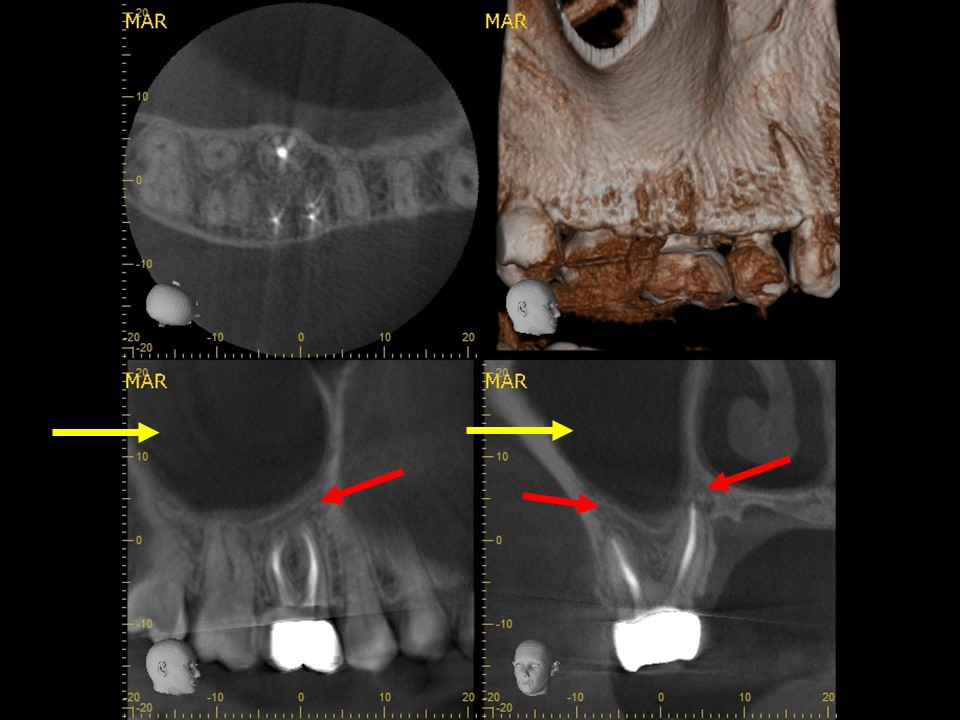

Case3 歯性上顎洞炎のケース

右上の6番の大臼歯に、大きなコンポジットレジン充填がしてありました。レントゲンおよびCT診査を行ったところ、歯髄に達する大きな充填の跡が見られ、根尖部の骨はすでに大きく溶けて吸収しており、炎症は副鼻腔に達していました(下写真)。レントゲンおよびCT画像から、虫歯治療後の歯髄壊死・壊疽から生じた慢性化膿性根尖性歯周炎と診断しました。また、根尖病変に起因する歯性上顎洞を併発していると診断しました。

治療前レントゲン | 治療前CT |

治療前レントゲン |

---|

治療前CT |

治療前のレントゲンおよびCT画像です。右上6番には歯髄に達する大きなコンポジットレジン充填がされています。

根尖部の骨は黒く大きく溶け(赤矢印)、ほぼ上顎洞と交通しています。

上顎洞内部は上方までX線不透過性が亢進し(白くなっています)、典型的な上顎洞炎の像を呈しています(黄矢印)。

予後確認・歯冠修復処置

根管充填3か月後のCT画像にて、根尖病変および歯性上顎洞炎の予後を確認しました。根尖病変は顕著に縮小して骨の再生が見られ、上顎洞炎はほぼ治癒していました(下写真)。

根管治療14か月後のレントゲン及びCT画像では、根尖部のX線透過像および上顎洞内の不透過像は完全に消失しているのが分かります(下写真)。根尖部の骨の再生と上顎洞の正常化が認められ、根尖病変ならびに歯性上顎洞炎は完全に治癒しました。

根管充填3か月後のCT画像です。根尖病巣は顕著に縮小しており、骨の再生を認めます(赤矢印)。上顎洞の炎症も消退し、ほぼ正常像を呈していることが分かります(黄矢印)。病状が治癒傾向を認めるため、歯冠修復処置を行っていきます。

根管治療14か月後のレントゲンおよびCT画像です。術前にあった根尖部のX線透過像(赤矢印)ならびに上顎洞内のX線不透過性の亢進(黄矢印)は完全に消失し、根尖病変および歯性上顎洞炎は良好に治癒しているのが確認できます。